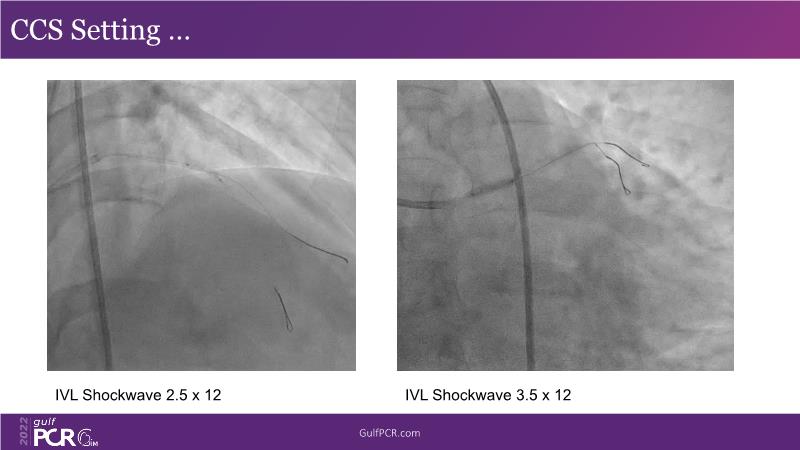

In this session, follow a LIVE case from the Chest Diseases Hospital in Kuwait and learn what the best strategy is to treat patients who present with a very long calcified coronary artery lesion, as well as how to select the best device and which different types of stents can be used.

- To learn correct interpretation of a long-calcified lesion and how to adopt procedural strategy